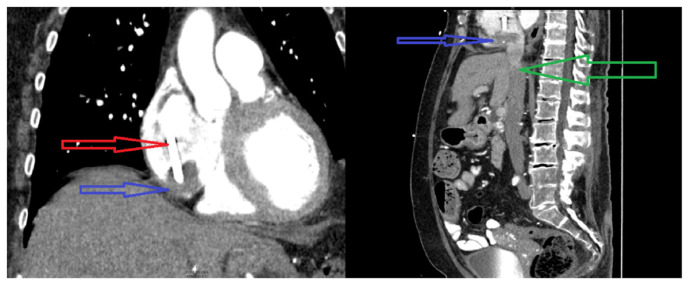

Intradialytic Atrial Fibrillation With Rapid Ventricular Response From Catheter-related Right Atrial Thrombus.

Right atrial thrombus is a rare complication of hemodialysis catheter with an incidence of <6 %. New-onset atrial fibrillation can be the first symptom of catheter-related right atrial thrombus (CRAT) in a patient with long-term dialysis catheter. Therefore, evaluation for CRAT is justified in such scenario. We highlight a case report where a new-onset atrial fibrillation led to the discovery of a right atrial thrombus in a patient with long-term dialysis catheter.